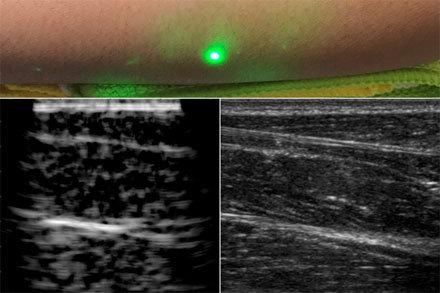

一種新的超聲波技術(shù)利用激光在皮膚下產(chǎn)生圖像,而不像傳統(tǒng)的超聲波探頭那樣與皮膚接觸。新的激光超聲技術(shù)被用來產(chǎn)生一個人類前臂的圖像(左),這也是使用常規(guī)超聲成像(右)。由X.Zhang等人提供。